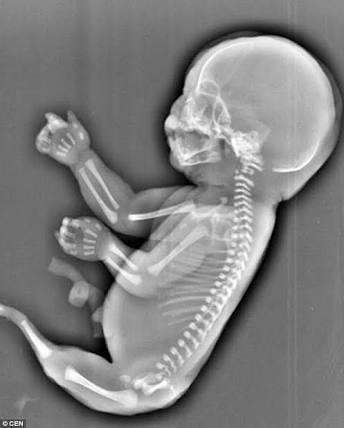

THE SCIENCE OF BABY DEVELOPMENT.... Fetal Development: Baby’s Bones and Skeletal System

A baby’s bones start developing soon after conception and don’t finish growing until she’s an adult.

It might be hard to believe when one is being poked from the inside by a pointy elbow or when a pointy little bottom is pushing on your bladder, but the baby’s bones don’t just grow in fully-developed. They are very much formed by what both individuals (mother and foetus) eat. The skeletal structure of a baby’s whole body starts out as a flexible cartilage that gradually ossifies ( becomes hard bone) as the baby absorbs more calcium from the mother during pregnancy and then from the foods intake (20 years beyond!).

Big changes are happening to the embryo. It’s starting to develop a clavicle and parts of a backbone, for starters, while the neural tube forms the source for parts of the nervous system as well as the spine and skull. By about week 6, the foetus is also sprouting arm buds as well as legs. the only thing that isn’t growing is its tadpole-like tail, that’s shrinking and will eventually disappear leaving only the tailbone at the base of the spine.

During these final weeks of your first trimester, your baby’s bones develop a lot. They start out as little buds and grow into recognizable arms and legs, with bendable joints and well-defined fingers and toes by about week 13. Upper limbs tend to lead the way by a few days, with lower ones following — the same way motor skills develop after your baby is born, from the top of the body down (lifting head, then pushing up, then crawling, then walking).

These are active months for bone-building. Your baby can now wiggle his limbs — you may begin to feel those first flutters of fetal movement sometime around week 18 (give or take a few weeks). If you get a peek at your baby during your week 20 ultrasound, you’ll now be able to see those bones he’s busy building — they’re finally visible.

At week 36, mother-baby calcium transfer peaks, with you passing along as many as 350 milligrams of the mineral every day for the remainder of your pregnancy. That’s the case even though your baby’s bones are still softer than an adult’s. They have to be, so they can fit through the birth canal around week 40 and allow room for growth once baby is born. Your baby’s skull, in particular, is designed for delivery: it’s made up of several separate bony plates that can shift and compress as your baby’s head makes its way toward the exit.